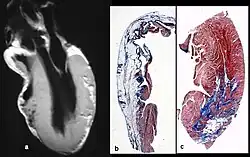

W przebiegu arytmogennej dysplazji prawej komory dochodzi do zaniku mięśni prawej komory oraz wynikającego z tego ścieńczenia ścian, powstawania tętniaka i jej powiększenia[10]. Niekiedy dochodzi do zajęcia lewej komory[10]. Choroba ujawnia się w wieku dziecięcym. Dominują objawy niewydolności prawokomorowej i komorowe zaburzenia rytmu. Nierzadko do rozpoznania może doprowadzić dopiero nagła śmierć sercowa – do 20% osób, które doświadczyły jej w ciągu pierwszych 35 lat życia było chore na ARVC[5]. Choroba stanowi częstą przyczynę nagłej śmierci u sportowców[5].

Stwierdzenie nacieków tłuszczowych w ścianie prawej komory.

- Dysfunkcje globalne lub regionalne i odmienności strukturalne (Rozpoznane w echokardiografii, angiografii, MRI lub scyntygrafii serca)

- Kryteria duże

- Znaczne poszerzenie i redukcja frakcji wyrzutowej prawej komory i brak lub niewielkie upośledzenie czynności skurczowej lewej komory

- Tętniaki prawej komory (obszary akinezy lub dyskinezy z diastolicznymi wybrzuszeniami). Znaczne odcinkowe poszerzenie prawej komory

- Zastąpienie miocardium tkanką włóknisto-tłuszczową stwierdzone w biopsji endomiokardialnej.